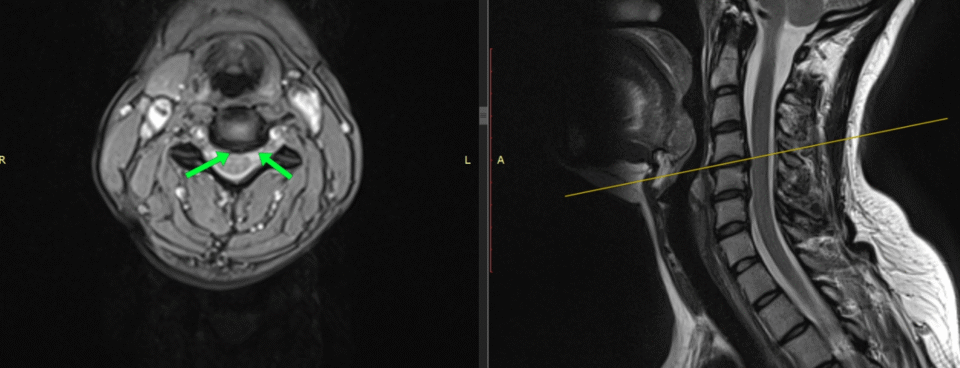

Tomografia komputerowa kręgosłupa – to badanie umożliwia postawienie bardzo precyzyjnej diagnozy. Pozwala na dokładne ocenienie struktury kostnej. Rezonans magnetyczny kręgosłupa – to jedno z najdokładniejszych badań diagnostycznych w przypadku dyskopatii. Pozwala na precyzyjne zobrazowanie krążków międzykręgowych oraz otaczających tkanek. Najczęściej jest wykonywane, gdy objawy bólowe są bardzo intensywne i nie ustępują mimo wdrożenia środków zapobiegawczych.